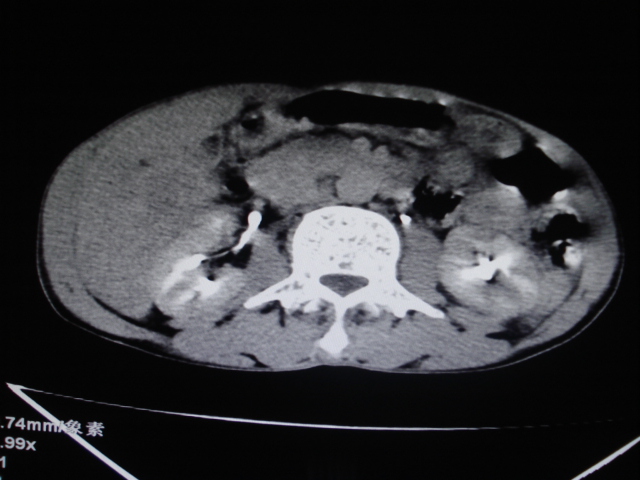

男性,62岁。肝右叶占位,平扫及增强如下,延迟期为15分钟扫描。

给病史及实验室检查!多考虑胆管细胞癌;右肾囊肿。

1)不均匀性脂肪肝。2)肝硬化。3)肝右叶肝癌不排除。4)右肾囊肿。